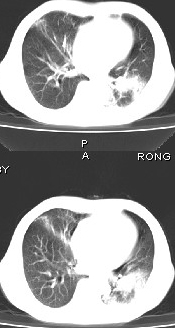

男68岁,反复发热、咳嗽,咯痰1月,曾有咯血史,双肺闻及呼吸音增粗。

左肺上叶尖后段及下叶多发实变阴影,内见支气管充气征,段以上支气管尚通畅,肺门区未见软组织肿块影,结合病人有反复发热病史,首先考虑感染性病变(干酪性肺炎不能排除),建议抗炎治疗后复查或结合纤支镜检查。

左肺上叶尖段及下叶干酪性肺炎可能性大,建议结合临床相关检查.右肺中叶炎症.建议治疗后复查.

该患者在25天前外圆平片见右肺中上肺野大片状影,(治疗不祥,在反复问病史后患者告诉;近一月住在新房内,搞装修),我认为首先考虑是感染,而且过敏性肺炎可能性大。